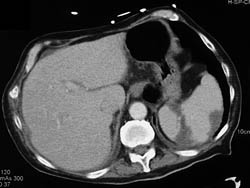

Old Subcapsular Hematoma